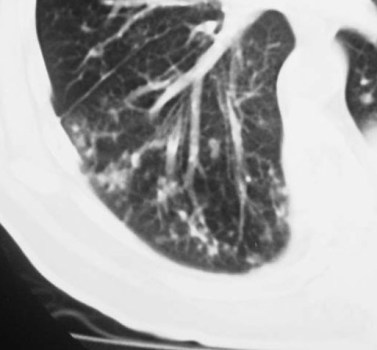

SIGNO DEL ANILLO DE SELLOANILLOSELLOSigno de bronquiectasia en la TC en ventana de parénquima. Cuando el bronquio dilatado tiene un trayecto vertical, en el corte axial aparece como una radiotransparencia circular con pared gruesa, acompañado de una arteria cuyo diámetro es más pequeño que el del bronquio (flecha).

La imagen recuerda a los anillos que tenían un escudo o marca personal con los que se autentificaban cartas o documentos mediante su impresión en lacre.